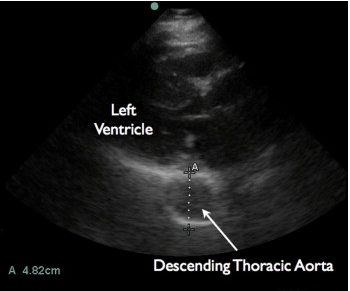

In a recent article in the Journal of Emergency Medicine, Dr. Resa Lewiss and friends, discuss 2 cases of thoracic aortic aneurysm identification by focused cardiac ultrasound. It is a great case report that highlights the need to include the aortic root and descending thoracic aorta in the parasternal long view of your focused cardiac echo.

“An 82-year-old man with hypertension presented to the ED with 1 month of chest pain radiating to the back. The focused cardiac ultrasound examination demonstrated enlargement of the descending thoracic aorta at 4.82 cm.”

Screen Shot 2014-03-04 at 9.17.06 AM